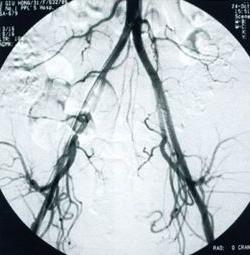

子宮輸卵管碘油造影。是診斷生殖器結核的較常用方法,一般於月經乾淨後3~7日內進行。可顯示如下特徵:①子宮腔呈不同程度的狹窄或畸形,邊緣呈鋸齒狀;②輸卵管管腔多處狹窄如串珠樣,或管腔細小而僵直;③在相當於盆腔輸卵管、卵巢、淋巴結的部位有鈣化灶;④若造影劑進入子宮一側或兩側靜脈叢,應考慮有子宮內膜結核的可能。雖然子宮輸卵管碘油造影對生殖器結核的診斷意義較大,但該操作有可能將輸卵管管腔中的乾酪樣物質或結核菌帶入腹腔,因此造影前後應使用抗結核藥物,結核活動期應避免該項檢查。超聲檢查 可探及盆腔包塊,界限不清,包塊內反射不均質,有時可見高密度鈣化反射。有結核性滲液時,可見盆腔積液或腹水徵象。臨床上有時易將生殖器結核誤診為卵巢腫瘤或炎性包塊。

(3)修復子宮附近的輸卵管損傷:如果子宮輸卵管造影顯示堵塞發生在子宮和輸卵管連線的地方,那么需要再用腹腔鏡術來確認是否真的損傷。如果僅僅是由於一些細胞碎片聚集形成堵塞,而非實際組織受到損傷造成堵塞,就不需要手術。只需用l根上端可活動的金屬絲,在它的牽引下醫師就可以將導管穿過子宮放入輸卵管。導管攜帶著1個充氣的小氣球來打開開口。對此過程的一項研究表明,熟練的醫師運用這種方法成功地打開了大多數輸卵管堵塞患者的開口。在治療後12個月內,懷孕率為39%,其中13%是宮外孕。